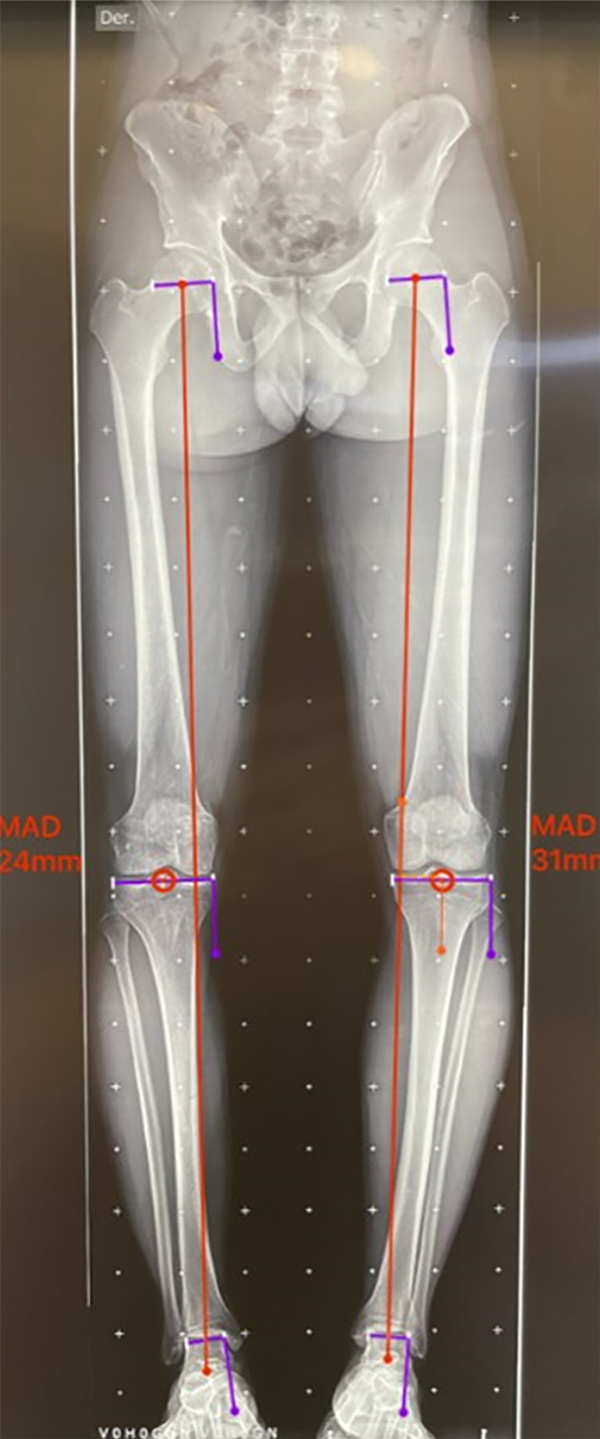

El paso 0 consiste en trazar una línea que va del centro articular de la cadera al centro articular del tobillo, recibe el nombre de “eje mecánico del miembro inferior” y el resultado fisiológico de esta medición es una línea que debe cruzar el centro articular de la rodilla con un rango de normalidad de desviación de 3 mm hacia medial o lateral.10 Al realizar la medición de la desviación, esta medida va a recibir el nombre de desviación del eje mecánico (MAD, por su nombre en inglés), según el cual, en caso de superar los 3 mm hacia medial, se trata de una deformidad en varo con un aumento de la carga en el compartimento medial de la rodilla; cuando el MAD se encuentra superior a los 3 mm laterales, es una deformidad en valgo y aumenta la carga del compartimento lateral de la rodilla21 (fig. 3).

Figura 3: Test de mal alineamiento: las líneas rojas corresponden al eje mecánico de los miembros inferiores, se marca el centro articular de la rodilla y se observa la desviación del eje mecánico o MAD derecho hacia medial de 24 mm, y en el izquierdo de 31 mm hacia medial, se evidencia una alteración de este valor con una deformidad en varo bilateral, con mayor predominio del lado izquierdo.